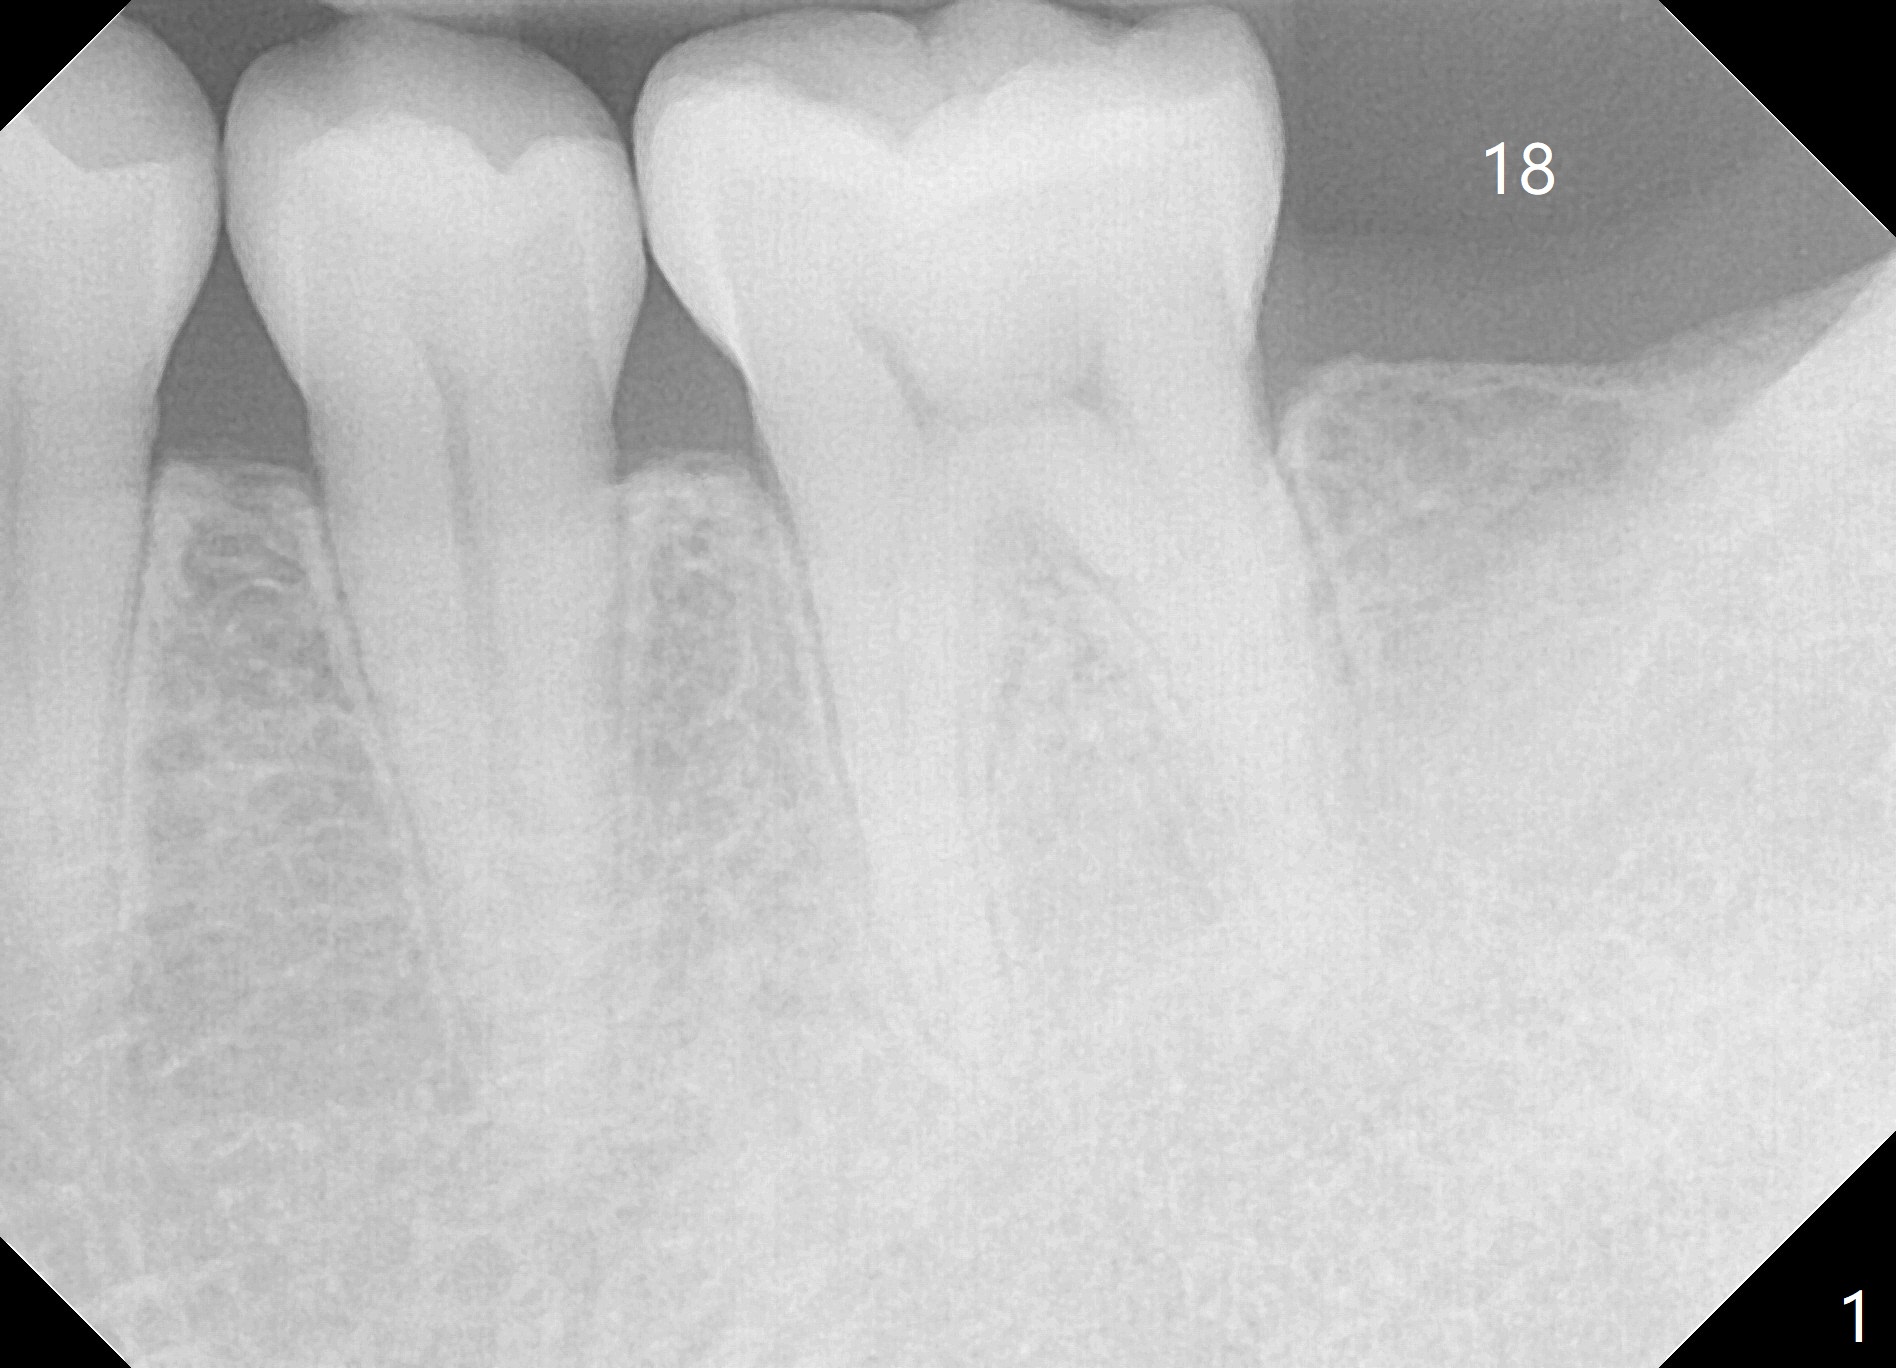

A 42-year-old man has lost #18 (due to 3rd molar impaction) for ~ 5 years (Fig.1). Because of the indistinct Inferior Alveolar Canal (Fig.3 ? vs. Fig.2 red dashed line), CBCT is taken for guided surgery (Fig.4: 5x11.5 mm).